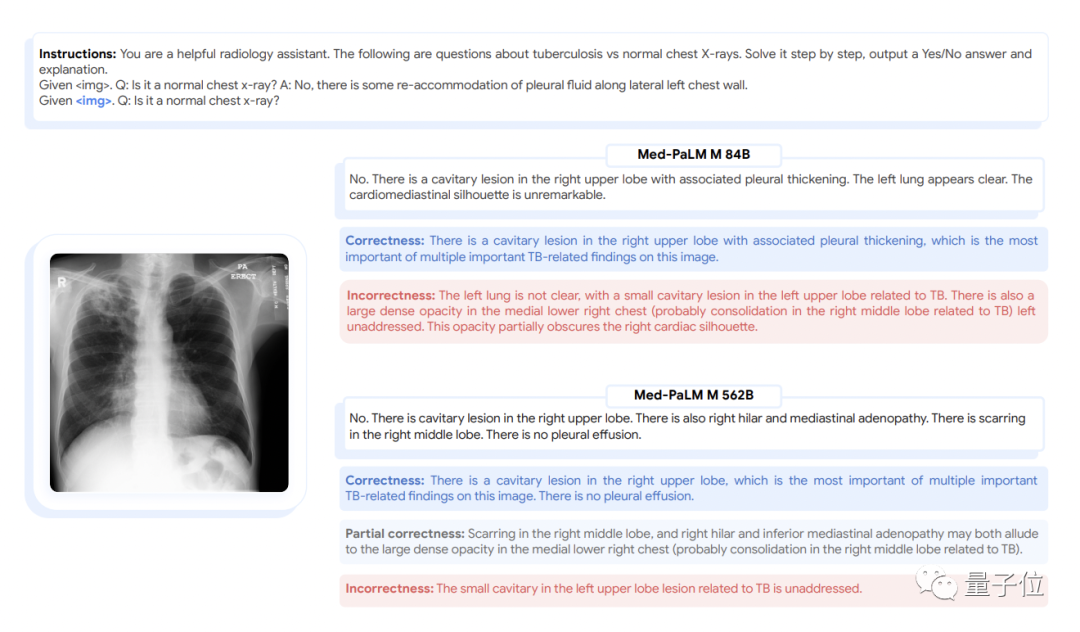

如下图所示的胸部x光解读和皮肤病变分类任务所示,这些指令有一种写提示语的味道,以“你是一个很给力的放射科助理”开头。

(3)零样本思维链推理能力涌现。Med-PaLM M可以通过胸部X射线图像检测没有训练过的结核病,与针对该类数据集进行专门优化过的SOTA结果相比,它的准确率已相差不大。

不过,它给出的具体报告还是存在具体错误,说明还有不足。